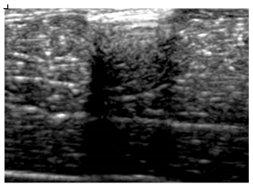

3.3. B-Mode Images

3.5. Echogenicity

4.1. Ultrasonography and Aerogel Dimensional Analyis

| Aerogel Type | US Image | Normalized Intensity Map | 3D Intensity Map | |

|---|---|---|---|---|

| 1 | Muscle |  |  |  |

| 2 | X-silica |  |  |  |

| 3 | X-silica-La2O2S:Eu |  |  |  |

| 4 | SMPU-Mix-14 |  |  |  |

| 5 | SMPU-Mix-18 |  |  |  |

| 6 | BRF-CA |  |  |  |

| 7 | ARF-CA |  |  |  |

| 8 | X-Ca-Alg-2 |  |  |  |

| 9 | X-Ca-Alg-1 |  |  |  |

| Aerogel Type | Imaging Frequency (MHz) | Optimal Frequency (MHz) | Echogenicity | Image Characteristics | Impedance Mismatch (%) | |

|---|---|---|---|---|---|---|

| Subcutaneous | Submuscular | |||||

| X-silica | 6.5–13.4 | 13.4 MHz | Hypoechoic | Least Hyperechoic | Distinct linear boundary | 92.03 |

| X-silica-La2O2S:Eu | 6.5–13.4 | 13.4 MHz | Hypoechoic | Least Hyperechoic | Distinct linear boundary | 90.28 |

| SMPU-Mix-14 | 6.5–13.4 | 11 MHz | Hyperechoic | Moderately Hyperechoic | Irregular boundary | 98.33 |

| SMPU-Mix-18 | 6.5–13.4 | 11 MHz | Hyperechoic | Moderately Hyperechoic | Irregular boundary | 98.23 |

| BRF-CA | 6.5–13.4 | 13.4 MHz | Hyperechoic | Hyperechoic | Waterfall appearance | 97.16 |

| ARF-CA | 6.5–13.4 | 13.4 MHz | Hyperechoic | Hyperechoic | Waterfall appearance | 97.12 |

| X-Ca-Alg-2 | 6.5–13.4 | 11 MHz | Isoechoic | Strongly Hyperechoic | Irregular boundary | 98.03 |

| X-Ca-Alg-1 | 6.5–13.4 | 11 MHz | Isoechoic | Strongly Hyperechoic | Irregular boundary | 97.97 |